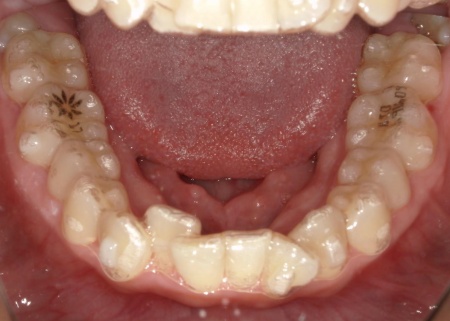

拝見したところ、歯が正しく並ぶためのスペースが不足しており、歯が重なって生えてしまう叢生(そうせい)の状態が全体的に見られました。

特に上下の糸切り歯が外側にずれている、いわゆる八重歯が目立っています。

また、矯正治療にあたって歯を並べるためのスペース確保が必要なため、以下2つの方法をお伝えしました。

①抜歯によるスペース確保:十分なスペースを確保しやすいものの、健康な歯を抜く必要がある

②歯と歯の間をわずかに削る「IPR」によるスペース確保:歯を残したままスペースを作ることができるが、削る量に限界があり適応できる症例が限られる

今回は②のIPRで対応できる範囲と判断し、メリット・デメリットを説明したうえで治療を開始しました。